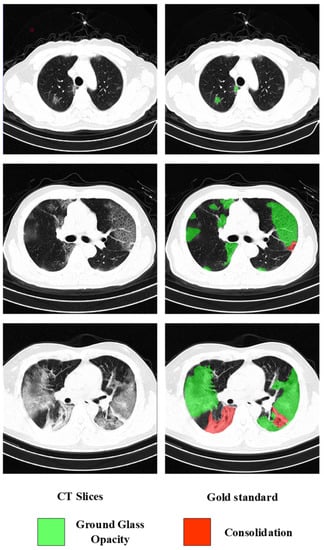

4.1.2. Lesion Segmentation Dataset (COVID19-Seg)

4.1.3. Lesion Segmentation Dataset (CC-COVID)